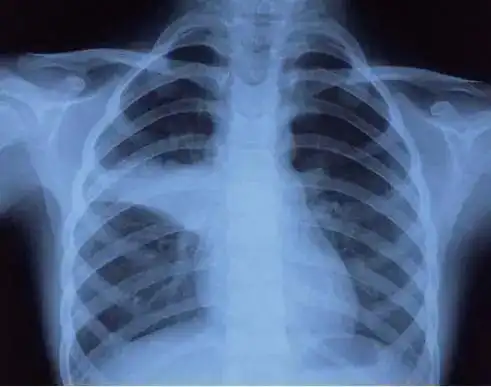

肺炎支原体来势汹汹,儿科专家支招如何防范